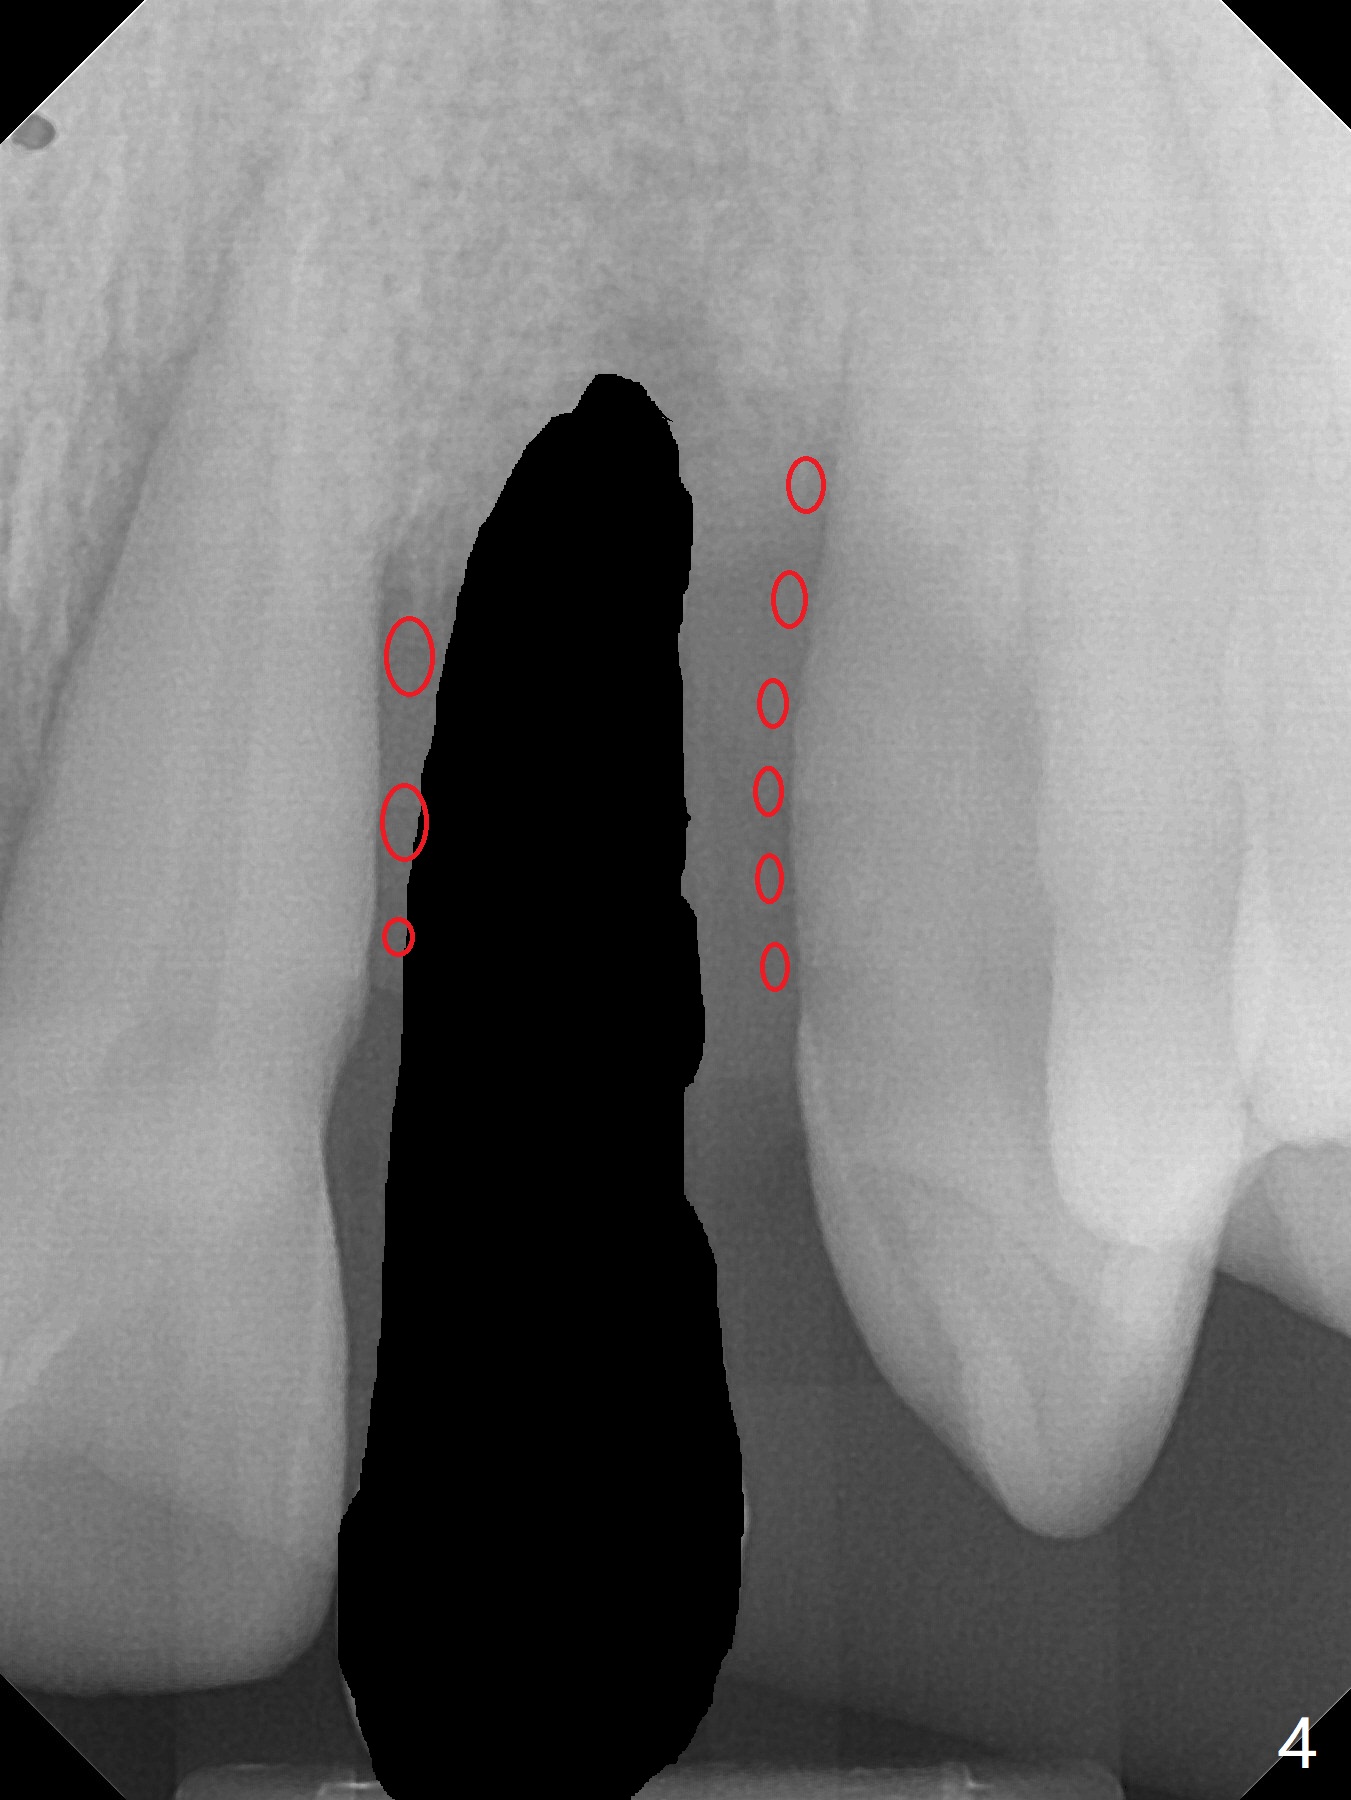

A 44-year-old man with generalized periodontitis (Fig.1) will return to clinic for #10 extraction (Fig.2) prior to brain tumor removal. Immediate implant (Fig.3) or not, sticky bone will be placed on the root surface of the neighboring teeth (Fig.4 red circles) after SRP. Place PRF membrane as early as possible, e.g, buccal, to avoid waste.